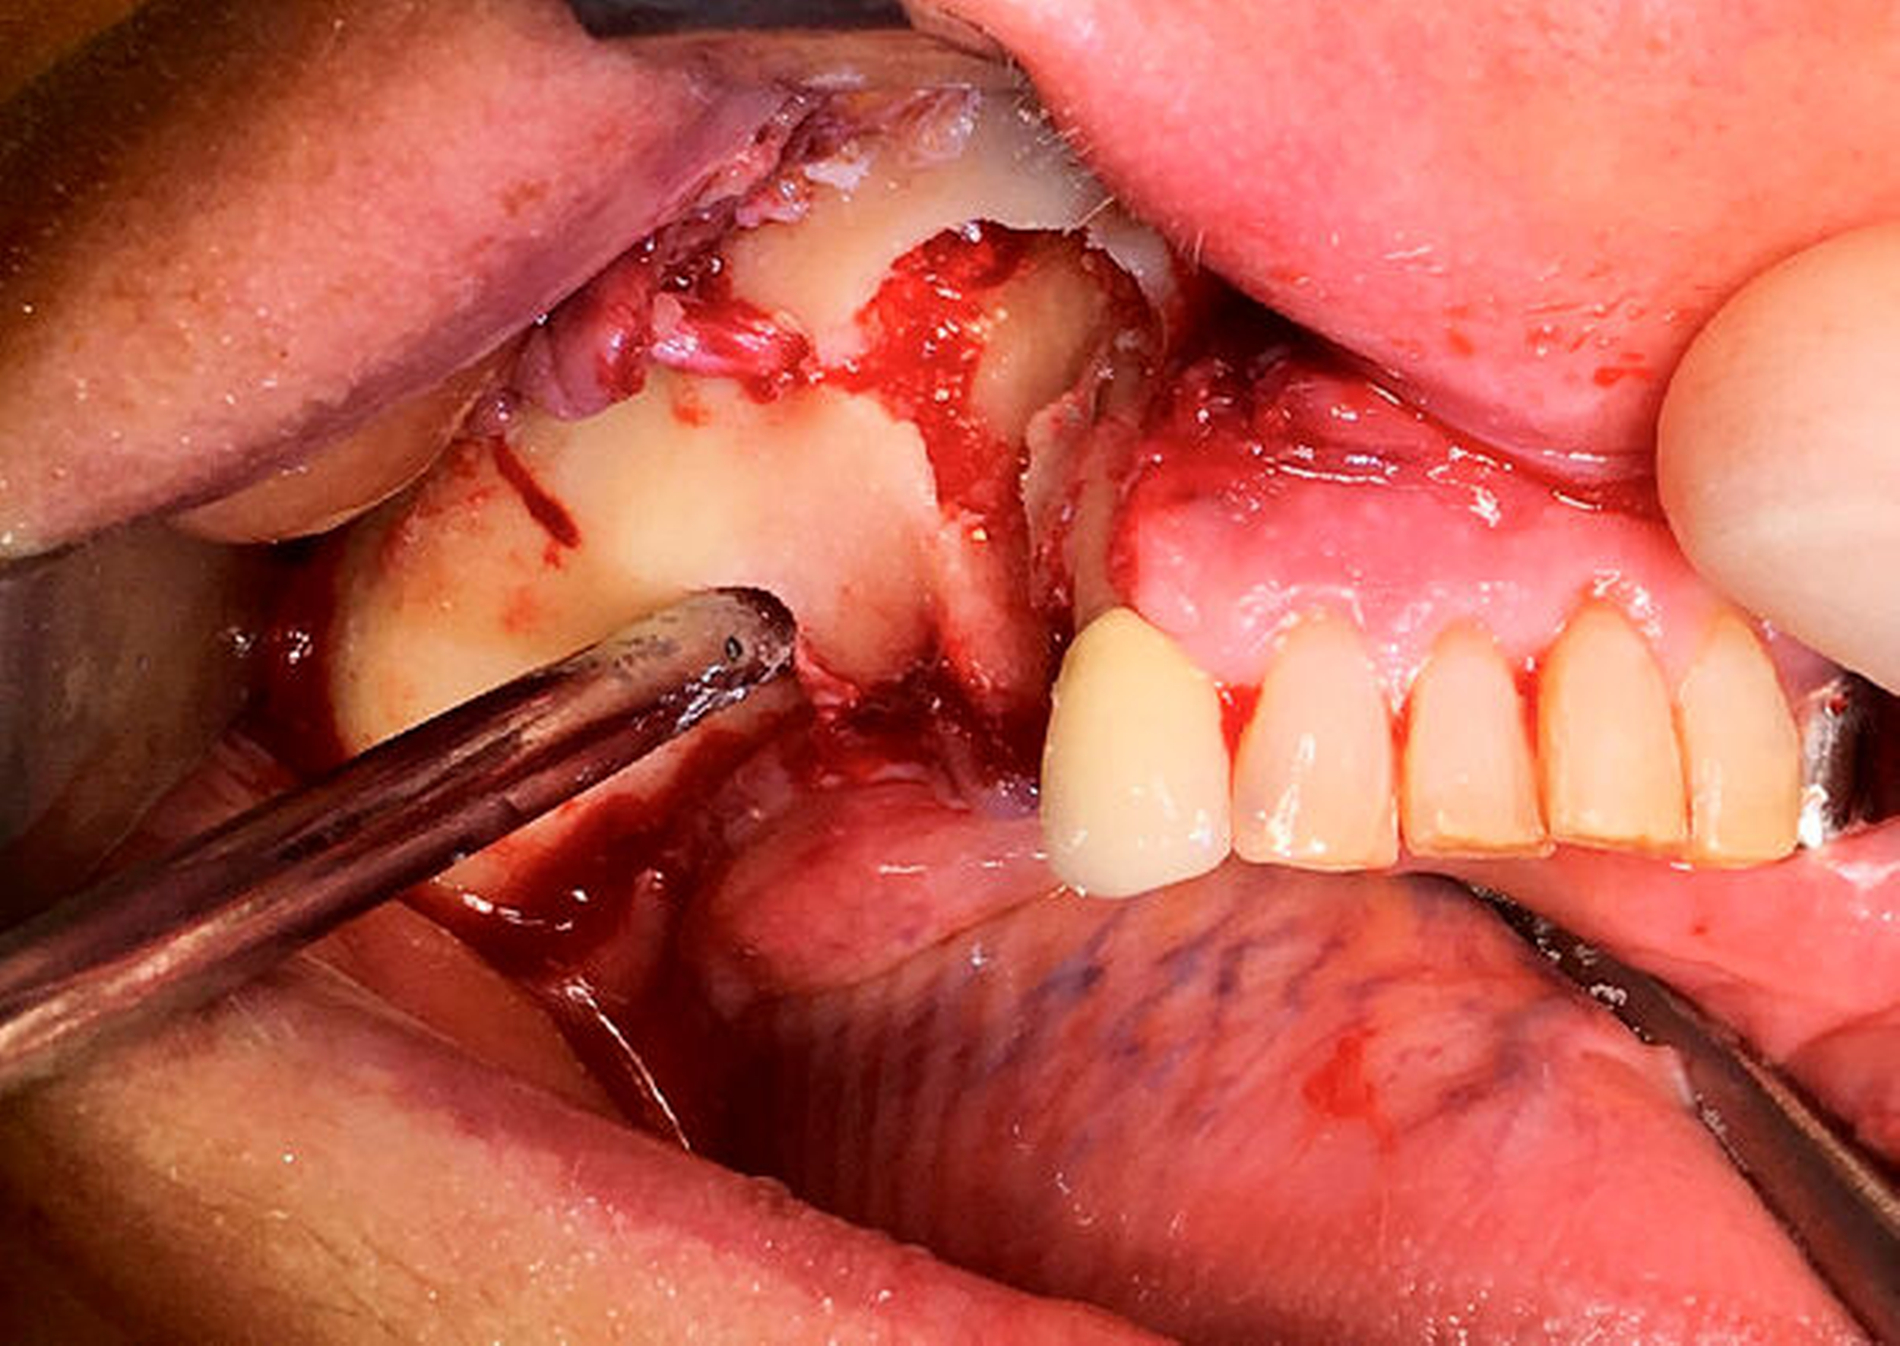

Nach der Entfernung des Wurzelrests 44 wurde der Nervus mentalis am Foramen mentale dargestellt und aus dem umgebenden Weichgewebe frei präpariert (Abbildung 6). Aus der Resektionshöhle und nach Entfernung der vestibulären Knochenlamelle auch aus dem Unterkieferkörper konnte anschließend der Sealer samt der extrem weichen Spongiosa entfernt werden. Die Lage der radiologisch dichten Verschattung im krestalen Bereich regio 36 konnte ebenfalls lokalisiert und problemlos entfernt werden. Bei dem Fremdkörper handelte es sich vermutlich um einen Amalgamrest (Abbildung 7).